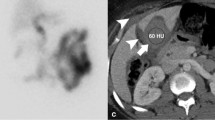

Hepatobiliary scintigraphy is a non-invasive modality that is more specific for bile leaks than US and CT and has a sensitivity that ranges from 64 to 100% [45, 49, 50]. It is limited by its poor spatial resolution and inability to confidently identify the bile duct involved, which is important for preoperative planning. The addition of single-photon emission computed tomography (SPECT–CT) improves localization of biliary leaks but also further increases radiation exposure [44, 51].